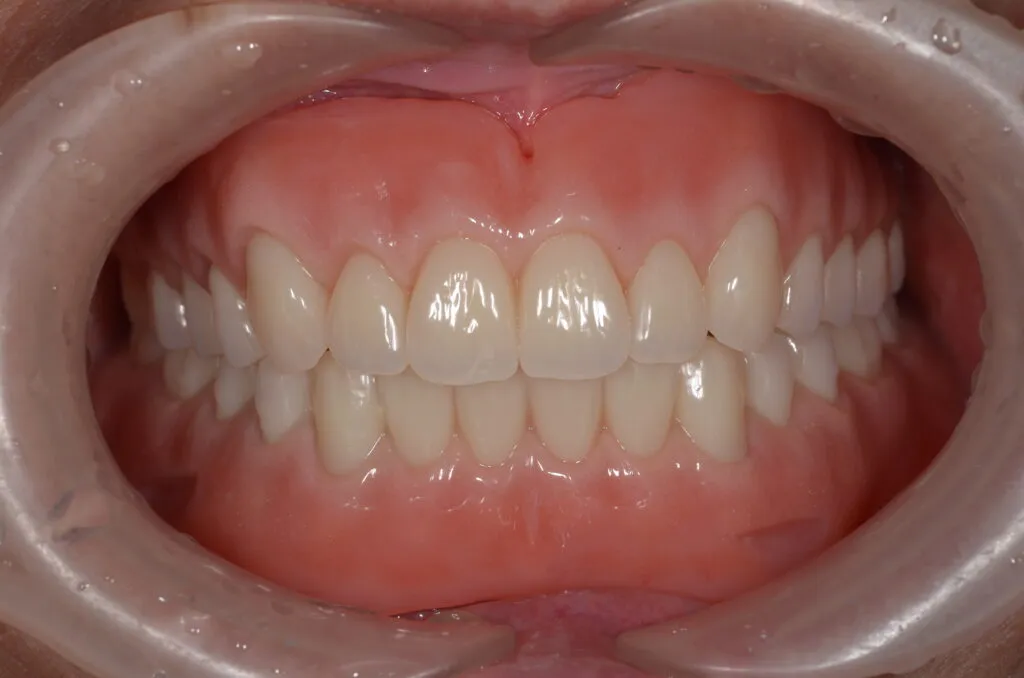

上記写真は当院で上下総義歯を作製した患者さんです

こちらの患者様の場合

【期間】2ヶ月

【費用】¥350,000~¥450,000/片顎(税抜)

【デメリット】精密に製作するため、保険の入れ歯よりも回数・費用がかかります。

上の写真は当院で上下総義歯を作製された患者さんです